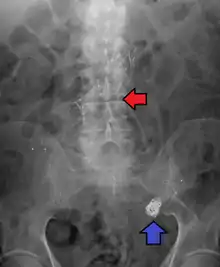

Diagnosis of a ruptured cerebral aneurysm is commonly made by finding signs of subarachnoid hemorrhage on a computed tomography (CT) scan. If the CT scan is negative but a ruptured aneurysm is still suspected based on clinical findings, a lumbar puncture can be performed to detect blood in the cerebrospinal fluid. Computed tomography angiography (CTA) is an alternative to traditional angiography and can be performed without the need for arterial catheterization. This test combines a regular CT scan with a contrast dye injected into a vein. Once the dye is injected into a vein, it travels to the cerebral arteries, and images are created using a CT scan. These images show exactly how blood flows into the brain arteries.[38]